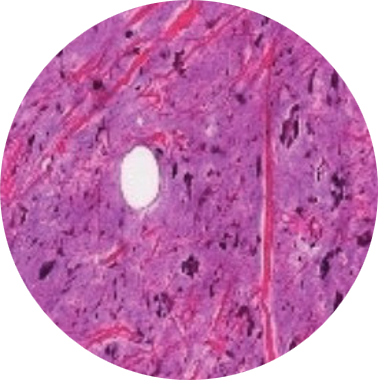

Histopatológico

O exame histopatólogico consiste na analise microscópica dos tecidos para a detecção de possíveis lesões existentes, com a finalidade de informar ao clinico a natureza, a gravidade, a extensão, a evolução e a intensidade das lesões, além de sugerir ou ate mesmo confirmar a causa da afecção. o objetivo final é fornecer o diagnóstico.

Colorações Específicas

A pesquisa de agentes infecciosos como, por exemplo, bactérias, fungos e bacilos álcool- ácido- resistentes, pode ser realizada por meio de colorações histoquímica adicionais, além da hematoxilina e eosina efetuada de rotina. O Lapac conta com um leque de colorações histoquímicas incluindo PAS (Mucina, glicogênio e fungos), Alcian-Blue (Mucina), Fite- Faraco (BAAR), Grocott-Gomori (Fungos), Vermelho-Congo (Amilóide), Giemsa (H.Pylori), etc.

Essas técnicas são realizadas nos mesmo blocos de parafinas utilizados no exame histopatológico.